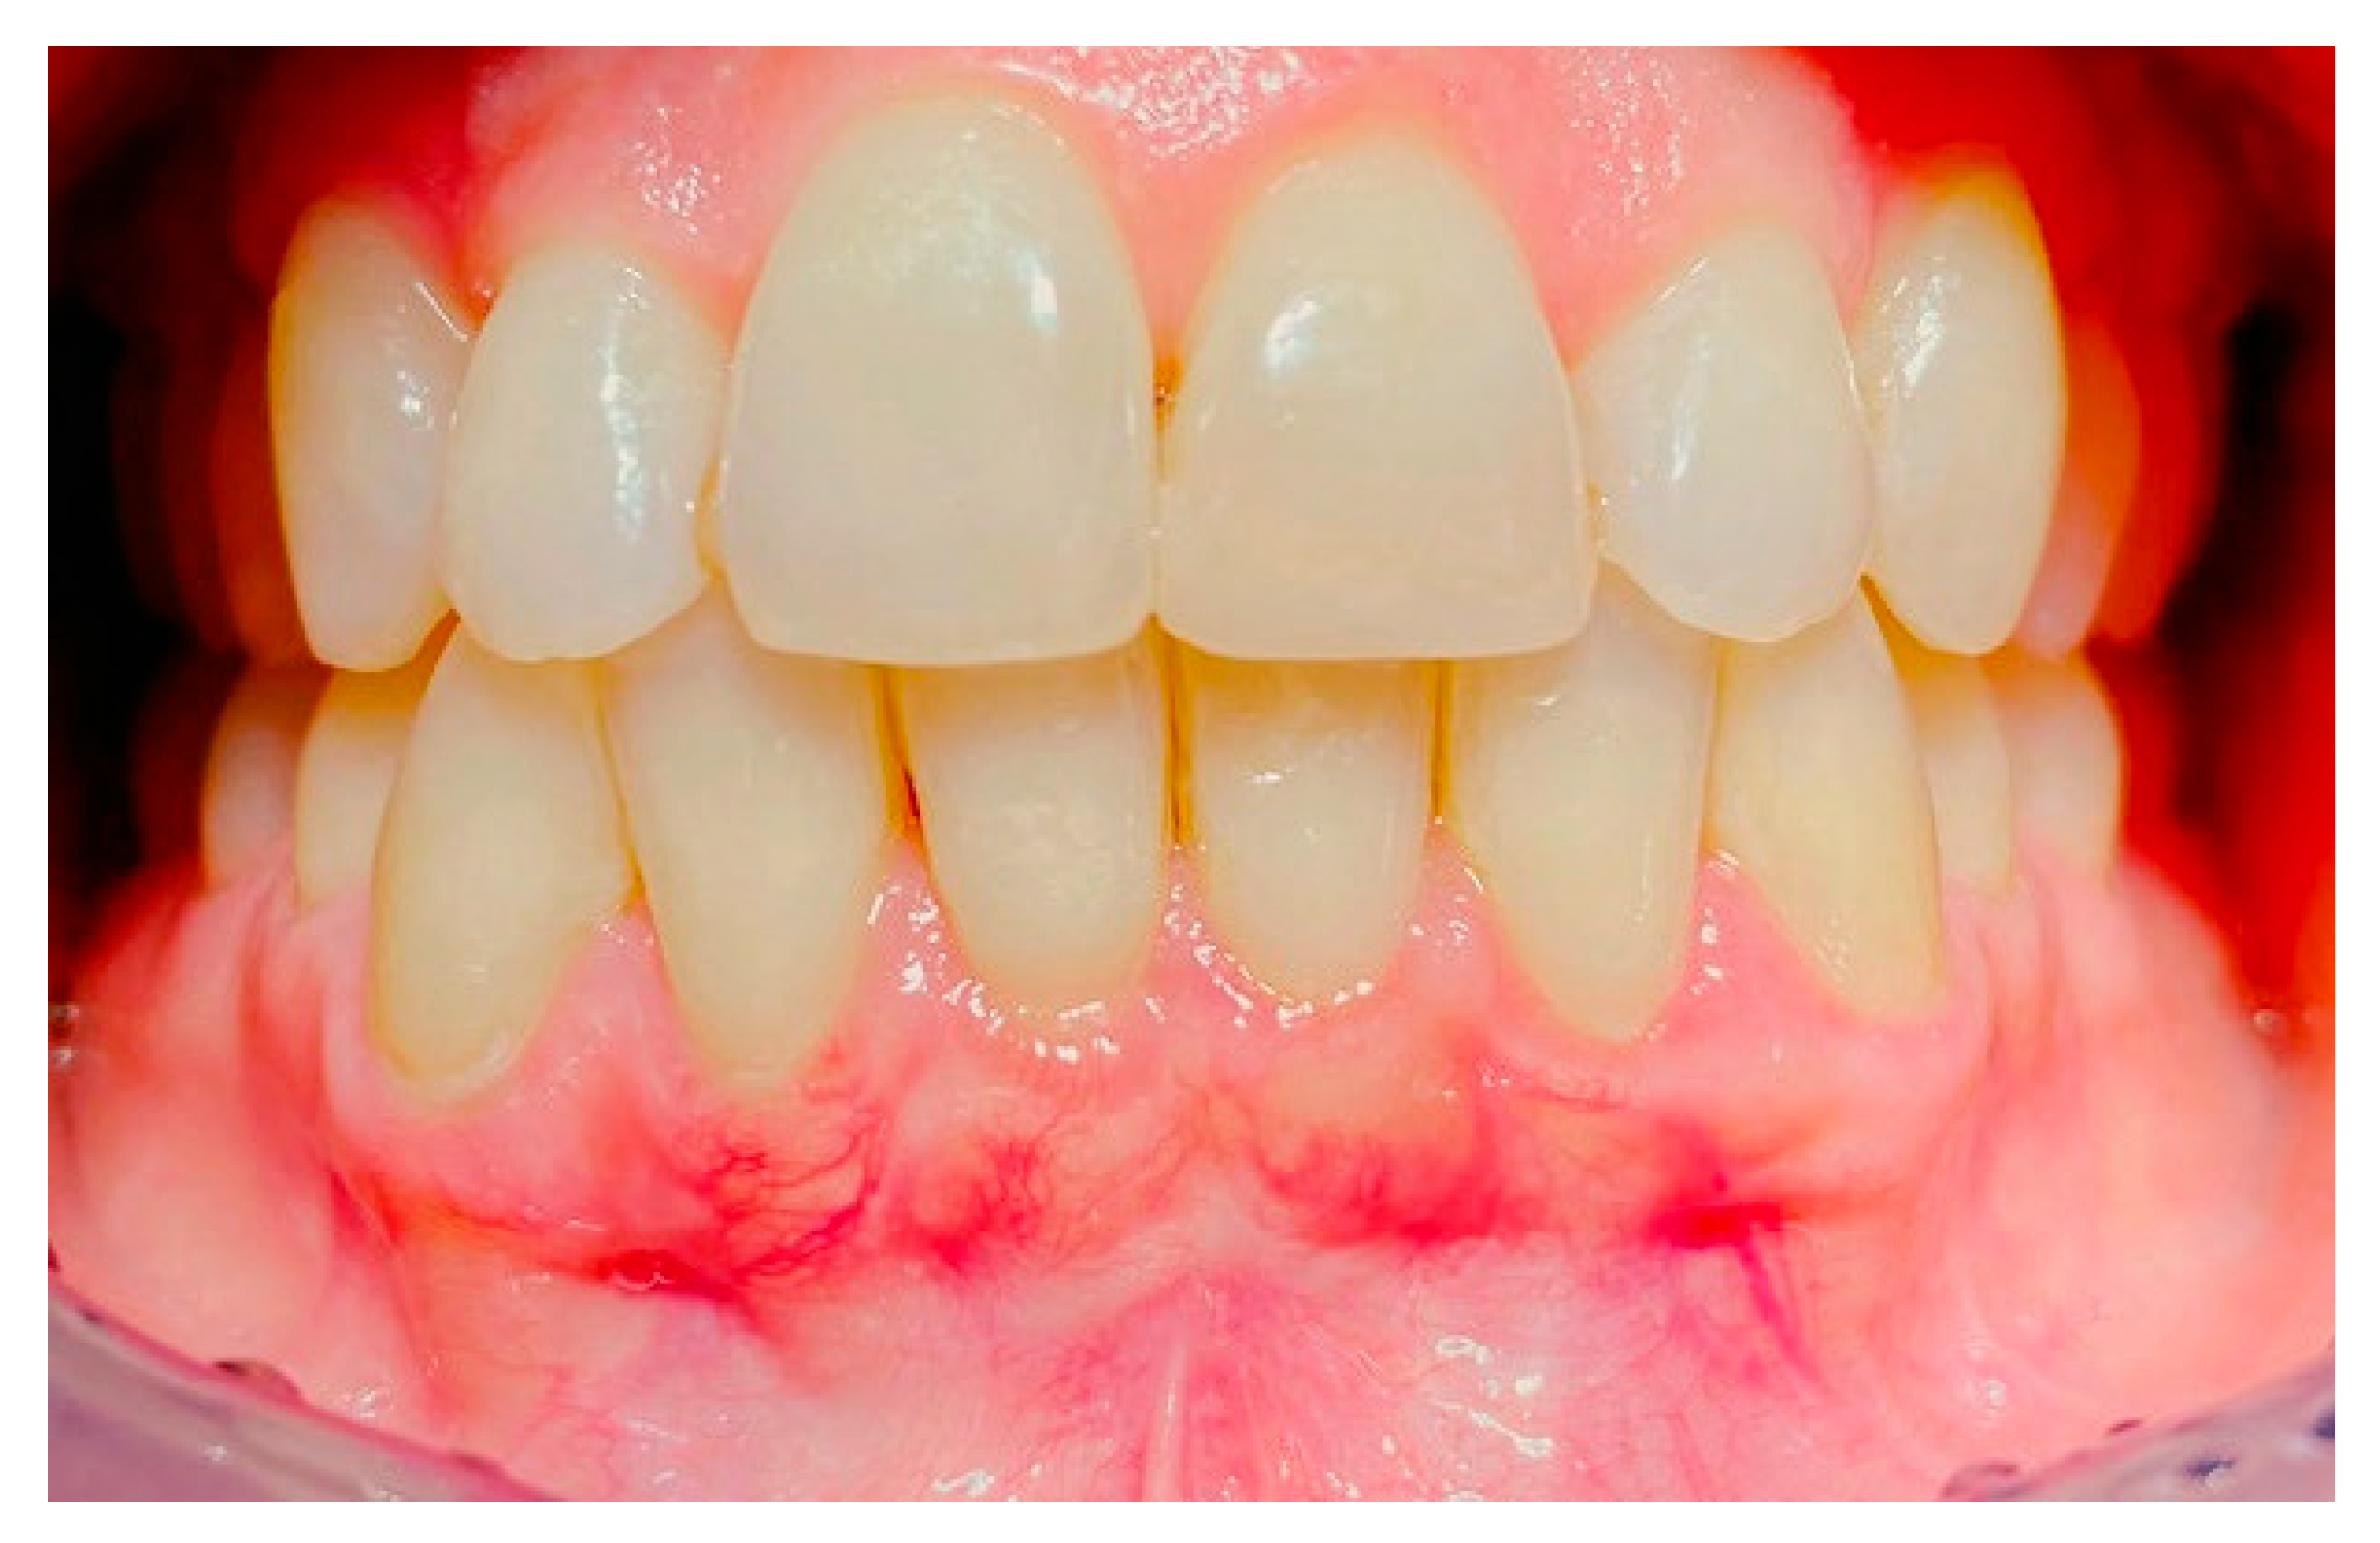

2. Case Study